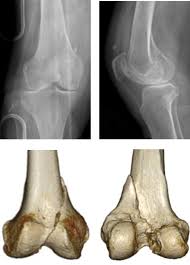

The radiographs demonstrated abnormal contour of the medial femoral condyle, consistent with an osteochondral defect, and a fabella posterior to the knee.

Of the six patients who had suffered an isolated fracture of their medial condyle, four of the patients had their fractures diagnosed on the first visit. The lateral condyle was involved in 44 % and the medial condyle in 12 %. It acts to support a significant amount of the patient's body weight. Cartilage can be focally damaged, producing a pot hole in the joint surface, when the knee ligaments are injured. Osteonecrosis of the medial femoral condyle presents as a sudden onset of pain on the medial side of the knee. A bone fracture at this location is termed a femoral condyle fracture. The femoral condyle is a thickened area of the femur just above the knee. One presumed mechanism of injury is a stieda fracture (avulsion injury of the medial collateral ligament at the medial femoral condyle). Root tear (radial tear) of the medial meniscus mild or moderate knee arthritis Coronal plane fracture of the lateral femoral condyle. The lesions were located on the medial femoral condyle in 8 (72.7%) cases and on the medial tibial plateau in 3 cases (27.3%). The medial femoral condyles are the bony protrusions on the inside edge of the bottom of the femur bone in each thigh. Based on the patient's antalgic gait and radiographic findings, the patient was instructed on the proper use of crutches and referred to an orthopaedic surgeon for appropriate management.

Methods sixteen knees with a small medial femoral. The lesions were located on the medial femoral condyle in 8 (72.7%) cases and on the medial tibial plateau in 3 cases (27.3%). Radiographic features it is almost always unilateral, usually affects the medial femoral condyle (but can occasionally involve the tibial plateau 9) and is often associated with a meniscal tear. In the knee, chondromalacia is usually related to injury, overuse of the knee, and poorly aligned muscles and bones around the knee joint. It acts to support a significant amount of the patient's body weight. Normal irregular ossification of the femoral condyles was present in 66% of the boys and 44 % of the girls 1 in a review of knee radiographs of 147 healthy, asymptomatic children between the ages of 3 and 13 years. The inner side of the knee or the medial femoral condyle is the most common area for a cartilage defect. A bone fracture at this location is termed a femoral condyle fracture. Palpable to either side of the knee joint when it is bent, they are known specifically as the medial and lateral femoral condyles. If there is a fracture (break) in part of the condyle, this is known as a fracture of the femoral condyle. Primary osteonecrosis of the femoral condyle shares several features with insufficiency fractures, including predominance in elderly women with factors responsible for mechanical stress (varum, obesity, trivial trauma), mechanical pain, and increased radionuclide uptake. An imbalance of the muscles around the knee (some muscles are weaker than others.) overuse (repeated bending or twisting) of the knee joint, especially during sports. Sagittal plane fracture of the medial femoral condyle.